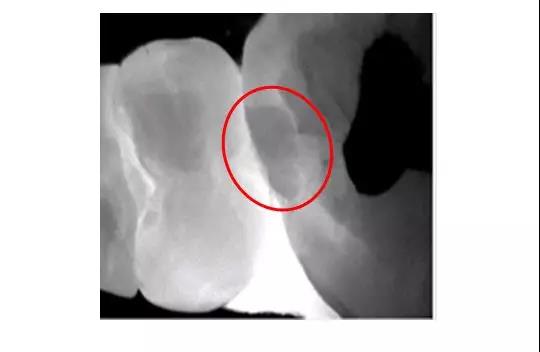

X光片

拍摄X光片显示:在X线片中未发现明显的近中邻面的低密度影像。